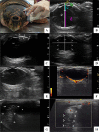

Background: Environmental changes contribute to the development of ophthalmic diseases in sea turtles, but information on their eye biometrics is scarce. The aim of this study was to describe ophthalmic ultrasonographic features of four different sea turtle species; Caretta caretta (Loggerhead turtle; n = 10), Chelonia mydas (Green turtle; n = 8), Eretmochelys imbricata (Hawksbill turtle; n = 8) and Lepidochelys olivacea (Olive ridley; n = 6) under human care. Corneal thickness, scleral ossicle width and thickness, anterior chamber depth, axial length of the lens, vitreous chamber depth and axial globe length were measured by B-mode sonography with a linear transducer. Carapace size and animal weight were recorded. A sonographic description of the eye structures was established.

Results: The four species presented an ovate eyeball, a relatively thin cornea, and a small-sized lens positioned rostrally in the eye bulb, near the cornea, resulting in a shallow anterior chamber. The scleral ossicles did not prevent the evaluation of intraocular structures, even with a rotated eye or closed eyelids; image formation beyond the ossicles and measurements of all proposed structures were possible. B-mode sonography was easily performed in all animals studied. The sonographic characteristics of the eye were similar among the four species. Since there was a correlation between the size of the eye structures and the size of the individual, especially its carapace size, the differences found between E. imbricata and Caretta caretta are believed to be due to their overall difference in size.